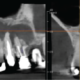

Periodontal bone levels are mainly normal or show mild bone loss, but there is greater bone loss associated with UR8 and UR7 and incidental finding of caries. UL4, UL5, UL6 sites have a mature alveolar ridge. No retained roots or bony pathosis. Selected images 3 are bucco-palatal cross-sections across the site. Bone height to the antral floor steadily falls moving distally across the site. There is a short transverse septum at the maxillary antral floor above the palatal side of UL5 site, which should not be relevant to any sinus lift procedure being planned. The alveolar bone quality appears satisfactory, with fairly dense trabeculation and well-defined cortices. The LL6 site has a mature alveolar ridge with no retained roots or bony pathothis. LL7 is mesially inclined, so that its crown overhangs the site. Selected images 4 are bucco-lingual cross-sections across the site. The alveolar ridge has a broad crest. There is a mild lingual undercut, with a lingual concavity present mesially in the site and in the premolar region. The lingual concavity of the submandibular fossa appears towards the distal end of the site. The ID canal is easily identified, lying quite low in the bone. The mental canal is in the plane of LL5. Bone quality is satisfactory, with well-defined thick cortices and fairly evenly trabeculated medullary bone.